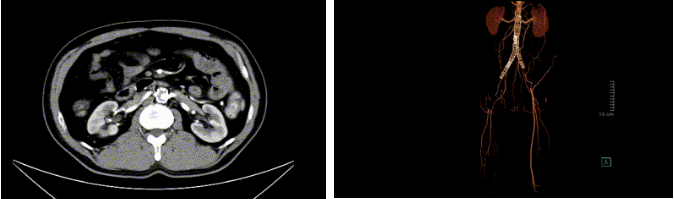

术前主动脉内支架及下肢动脉血栓形成,完全闭塞

针对刘先生的情况,在张喜成主任的主持下,血管外科与介入科全体医生进行了深入的探讨并制定了2套治疗方案:第一种是介入手术,尽管微创损伤小,但患者存在免疫性疾病,再次介入治疗不仅远期通畅率难保证,仍可能反复闭塞,且费用高昂;第二种是外科开腹人工血管搭桥手术,鉴于患者存在腹膜后纤维化,手术难度大,创伤略大,但远期通畅率会高,且费用较低。将手术方案与刘先生充分沟通后,最终医生们为刘先生实施了主动脉-双侧股动脉的架桥手术。在麻醉科、手术室同仁的大力支持和默契配合下,张喜成主任主刀,孙元副主任医师、黄献琛副主任医师协助,共同为刘先生实施了腹主动脉-双侧股动脉人工血管搭桥术。术中发现患者主动脉与周围组织粘连严重、血管壁脆弱,很难分离,但手术团队凭借过硬的技术,游离出合适的主动脉,去除部分的支架,经过3个半小时的努力,成功完成“架桥”手术。患者安全返回病房,在医护人员的精心治疗与护理下,刘先生恢复迅速,下肢缺血症状完全缓解,复查主动脉CTA,搭桥人工血管血流通畅。

复查主动脉CTA,搭桥人工血管血流通畅。